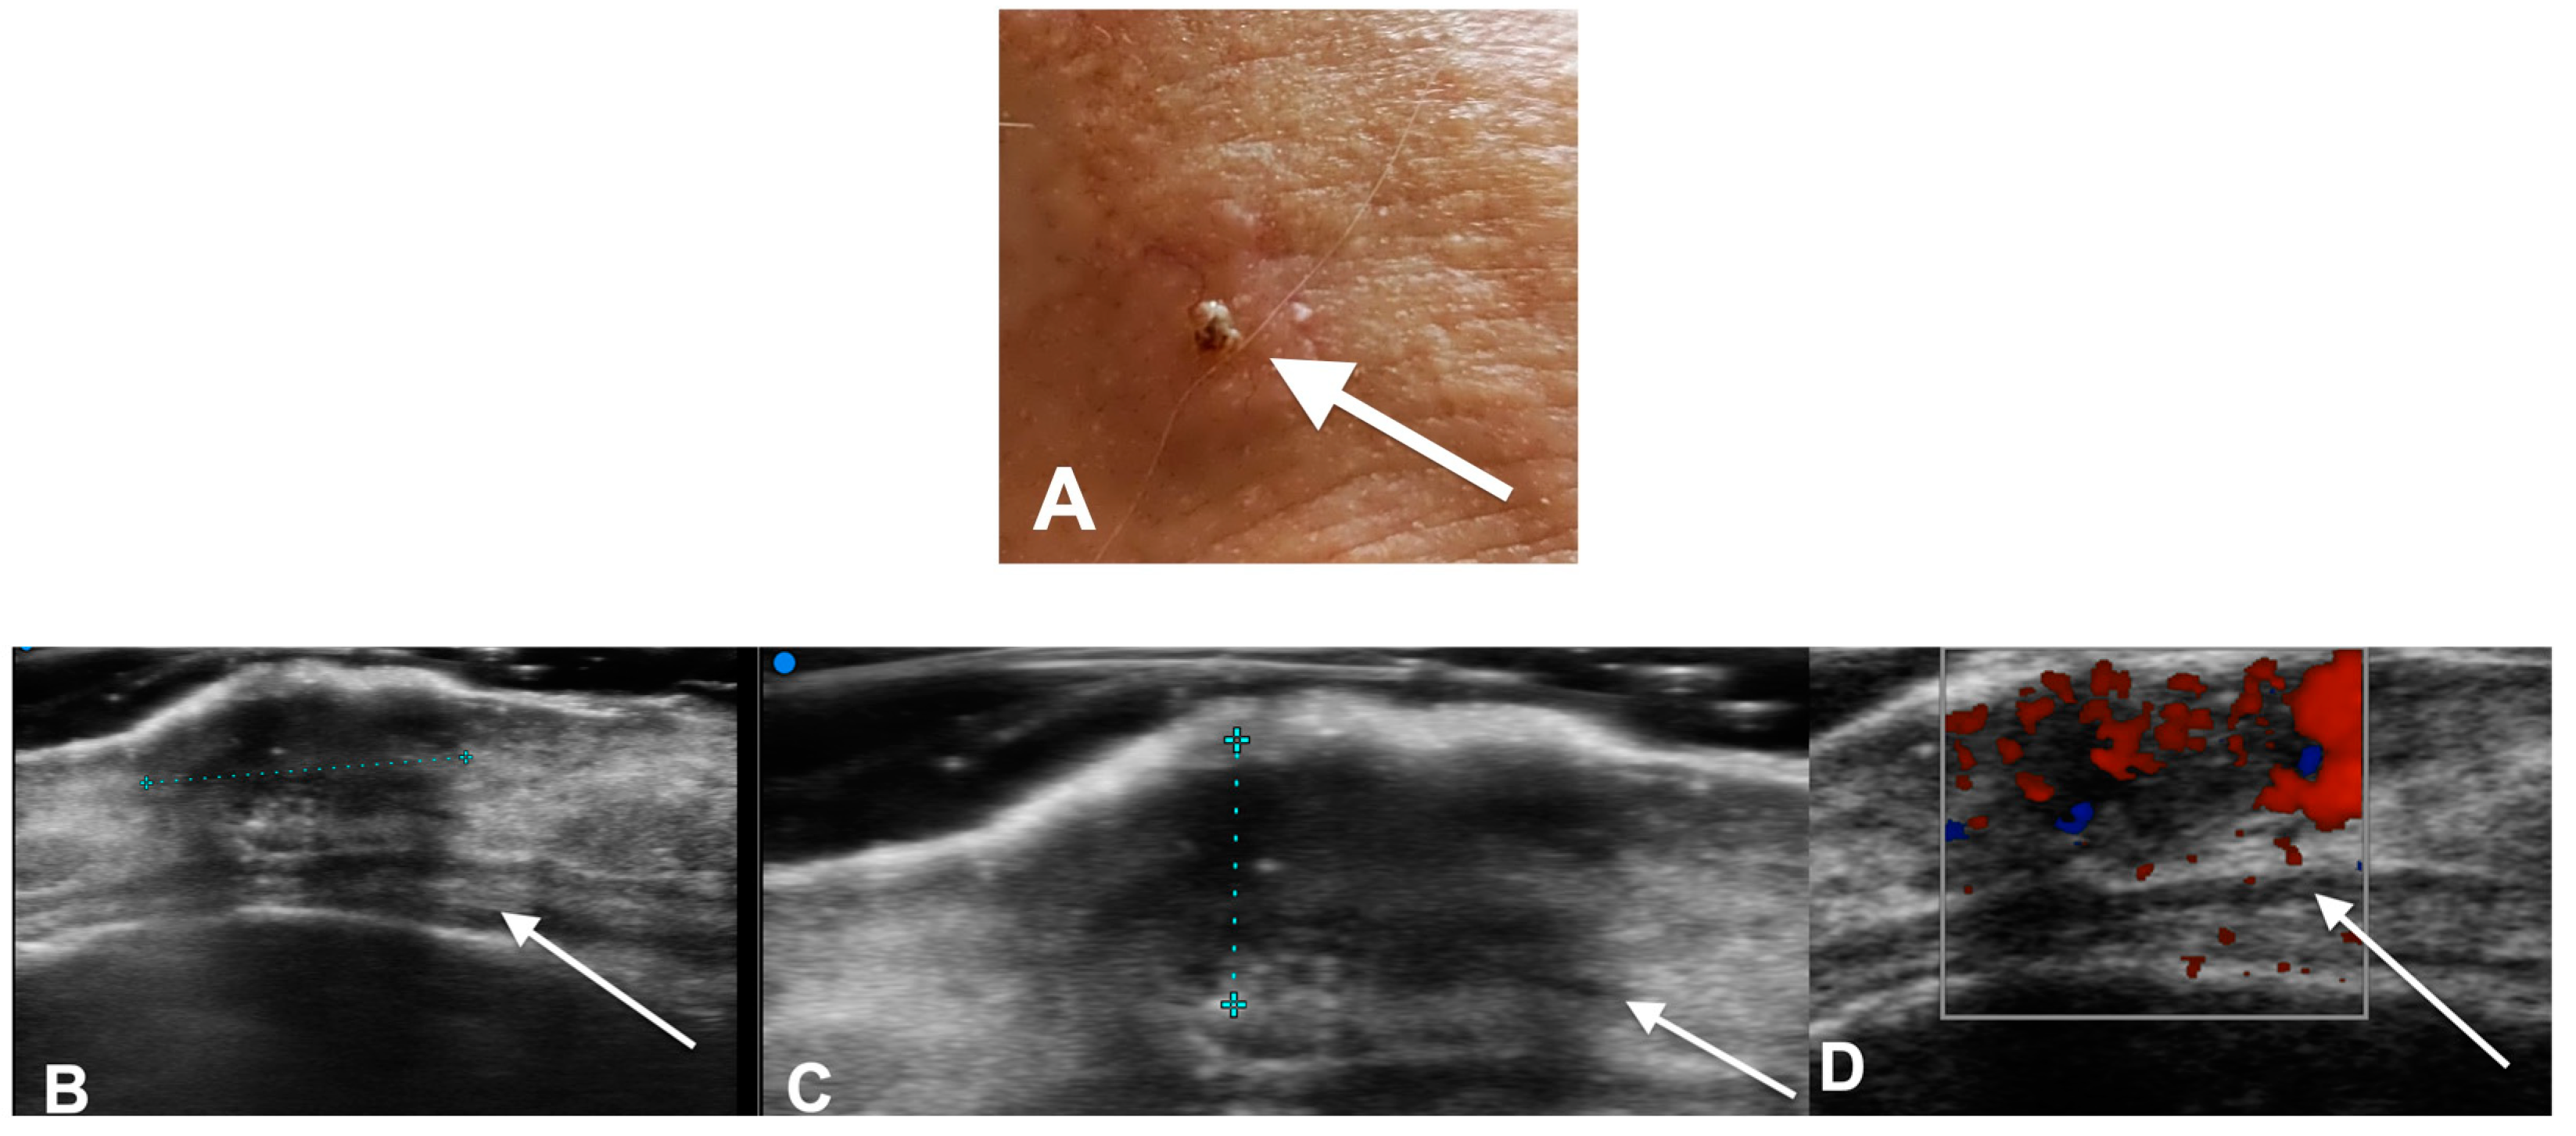

- Zhu, A.Q.; Wang, L.F.; Li, X.L.; Wang, Q.; Li, M.X.; Ma, Y.Y.; Xiang, L.H.; Guo, L.H.; Xu, H.X. High-frequency ultrasound in the diagnosis of the spectrum of cutaneous squamous cell carcinoma: Noninvasively distinguishing actinic keratosis, Bowen’s Disease, and invasive squamous cell carcinoma. Ski. Res. Technol. 2021, 27, 831–840. [Google Scholar] [CrossRef] [PubMed]

- Catalano, O.; Roldán, F.A.; Varelli, C.; Bard, R.; Corvino, A.; Wortsman, X. Skin cancer: Findings and role of high-resolution ultrasound. J. Ultrasound 2019, 22, 423–431. [Google Scholar] [CrossRef] [PubMed]

- Reginelli, A.; Belfiore, M.P.; Russo, A.; Turriziani, F.; Moscarella, E.; Troiani, T.; Brancaccio, G.; Ronchi, A.; Giunta, E.F.; Sica, A.; et al. A Preliminary Study for Quantitative Assessment with HFUS (High- Frequency Ultrasound) of Nodular Skin Melanoma Breslow Thickness in Adults Before Surgery: Interdisciplinary Team Experience. Curr. Radiopharm. 2020, 13, 48–55. [Google Scholar] [CrossRef]

- Belfiore, M.P.; Reginelli, A.; Russo, A.; Russo, G.M.; Rocco, M.P.; Moscarella, E.; Ferrante, M.; Sica, A.; Grassi, R.; Cappabianca, S. Usefulness of High-Frequency Ultrasonography in the Diagnosis of Melanoma: Mini Review. Front. Oncol. 2021, 11, 673026. [Google Scholar] [CrossRef]